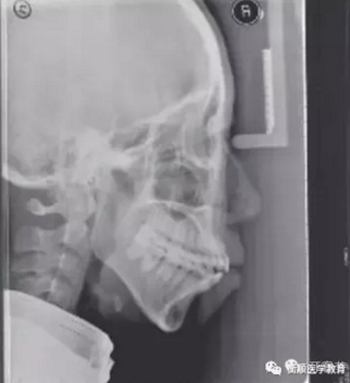

圖2 治療前頭顱側位片